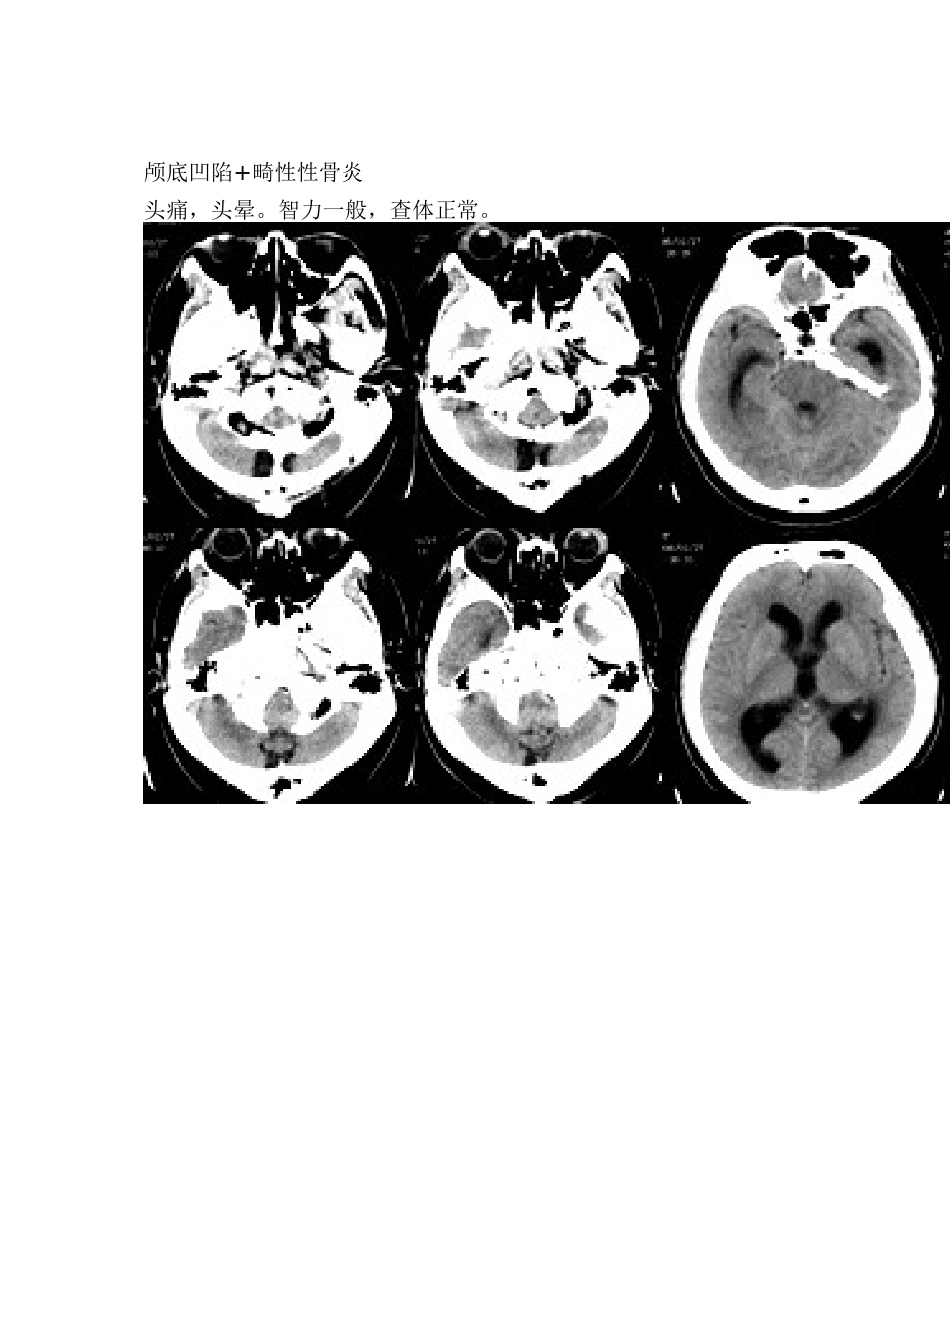

颅底凹陷+畸性性骨炎头痛,头晕。智力一般,查体正常。颅底凹陷:是指枕大孔周围骨如枕骨斜坡及岩骨向颅腔内陷入而言。分为先天及后天性,前者常并发于上部颈椎畸形,后者常继发于颅底骨硬度减低者,如畸形性骨炎(PAGET病),成骨不全,佝偻病,软骨病等,此时,变软的颅底受到颈椎的压迫,出现颅底内陷。畸形性骨炎:(PAGET病),是一种原因不明的慢性进行性骨病,多骨受累,最易累及骨盆,腰椎,颅骨,股骨,胫骨,很少累及腓骨,胸骨,其病理改变为破骨与成骨改变,初期以破坏为主,缓解期破坏停止,成骨继续进行,骨由松软变脆硬,其典型X线表现常出现在修复期成骨过程中,可出现活动期以骨吸收为主的海绵型及修复期以成骨为主的硬化型改变,颅骨板障明显增宽,内外板不规则增厚,当颅骨外板还有疏松性变化时,内板就可硬化,此为畸形性骨炎最重要的特征表现。故该列为典型的畸形性骨炎继发颅底凹陷。畸形性骨炎病因不明,目前认为与麻疹病毒感染有关,多见于40岁以上的男性,全身骨骼以骨盆发病率最高,本病一般发病隐潜,发病缓慢,病程较长,症状出现变异很大,常数年或数十年除骨关节畸形外,可无任何明显症状,常见症状为腰背痛和肢体畸形。实验室检查碱性磷酸酶常显著增高,有时可达100或200布氏单位以上。畸形性骨炎的特征是在发病过程中同时出现骨质吸收和骨质增生,新生骨骨化不全,结构杂乱,完全改变了正常的骨结构。因此,虽有骨质增粗增厚,但质软,容易发生畸形和病理骨折。通常在早期骨吸收显著,晚期则以增生为主,有的可恶变为骨肉瘤。本病应与骨转移鉴别,主要鉴别点为:本病有骨体积增大、畸形改变,以及病史较长、碱性磷酸酶升高等。女,56岁,头痛,没有其他的神经系统的阳性体征结果:颅底凹陷征颅底陷入是枕大孔周围骨,包括枕骨基底部、髁部和鳞部上升向颅腔内陷入的畸形。环、枢椎也随之上升、突入。多属枕骨及环枢椎先天性发育异常,也可继发于引起颅底软化的疾病、成骨不全或佝偻病等。21岁,颅骨发育异常结果:佝偻病颅骨软化颅底凹陷症